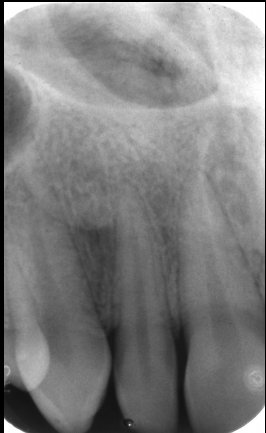

Radiographic appearance of hypercementosis

Excessive amounts of cementum on the root. Cementum = less radiopaque than dentin. PDL and lamina dura around excessive cement.